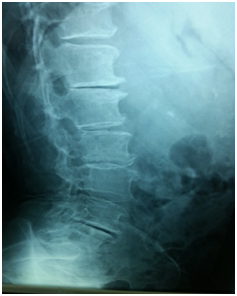

Flat back syndrome

- Loss of Lumbar Lordosis.

- Need an extensive release of the posterior elements with facet joints osteotomy.

- Anterior release MAY also be needed in severely rigid curves.

- Anterior column reconstruction with cages especially at Lumbo- sacral junction is necessary and always required to restore sagittal balance (Figure 3).

Figure 3 Flat back syndrome.